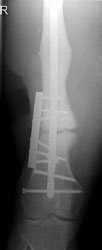

Abbildungen 1 und 2 zeigen einen typischen Defekt der konturgebenden Knochenprojektion im Frontzahnbereich, wie er z. B. – wie hier dargestellt – nach Trauma oder Entzündung entstehen kann (Abb.1 und 2).

Die Rekonstruktion sollte insbesondere in diesem sensiblen Bereich nicht simultan mit der Implantation, sondern präimplantologisch erfolgen. Die Rekonstruktion der sagittalen Projektion im Frontzahn- sowie der transversalen Projektion im Seitenzahnbereich der Juga alveolaria stellt einen hohen Anspruch an die chirurgische Behandlung dar, zumal die Wiederherstellung der gemeinsam mit der Hartgewebsunterlage geschrumpften Weichgewebsdecke bereits vor Behandlungsbeginn berücksichtigt werden muss. Bei Patienten mit hoher Lachlinie, eigentlich aber in jedem Fall der Rekonstruktion des Alveolarfortsatzes, muss die ursprüngliche Projektion nicht nur wiederhergestellt, sondern sogar leicht überdimensioniert gestaltet werden, da das Implantat – gegenüber einer natürlichen Zahn wurzel – von 1 mm – 1,5 mm Knochen allseitig umgeben sein sollte.